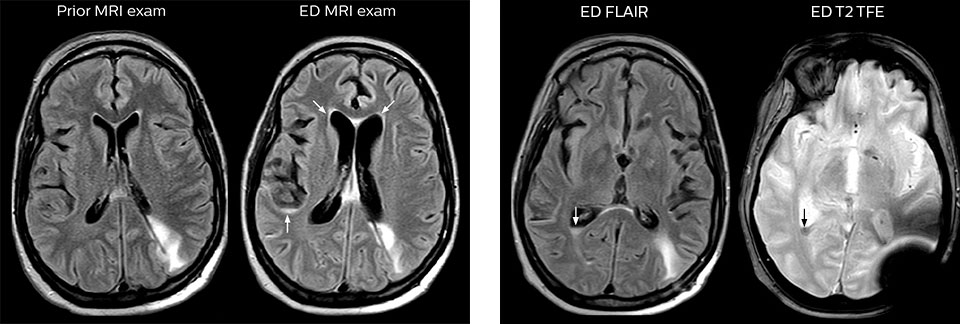

“We use mDIXON TSE extensively in our spine imaging in the emergency room,” says Dr. Karis. “It’s particularly nice in that it is very robust with regard to susceptibility type of problems that would come up with traditional spectral fat-saturated images; these problems are essentially eliminated with the mDIXON technique. In our ED environment it’s really nice to have the fat-free imaging that goes along with the mDIXON technique.

“For the thoracic and cervical spine routine non-contrast exam, for example, we perform one mDIXON T2 TSE sequence, which provides us with two outputs: the fat-and-water-together T2-weighted images, as well as the water-only sagittal T2-weighted images. And then we also perform an axial gradient echo exam.”

“Before, when patients received CT in the ED, it was quite common that they would need an MRI afterwards. However, in the four months that I have logged data for this study, I have not become aware of a single patient that underwent MRI in the ED and had to come back for repeat imaging, probably because the protocols are so robust. Patients with complicated cases requiring specialty acquisition types are the most common reason for recalls at our institution.”

“Our results show that a dedicated MRI in the ED can be effectively implemented; patient turnaround times with MRI were on par with CT. Interestingly, even though the MRI exam protocols were shortened, this robust yet rapid scanning still yielded good quality images, further improving our workflow and almost eliminating the need for repeat scans or follow-up scans. So, we’re heading towards first time right imaging,” says Dr. Karis.